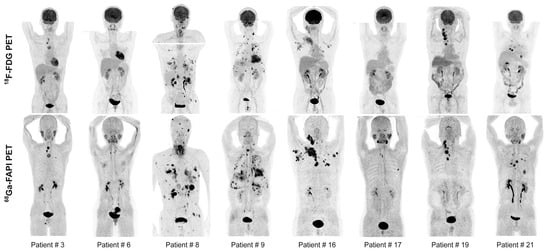

- Kratochwil, C.; Flechsig, P.; Lindner, T.; Abderrahim, L.; Altmann, A.; Mier, W.; Adeberg, S.; Rathke, H.; Röhrich, M.; Winter, H.; et al. 68Ga-FAPI PET/CT: Tracer Uptake in 28 Different Kinds of Cancer. J. Nucl. Med. 2019, 60, 801–805. [Google Scholar] [CrossRef]